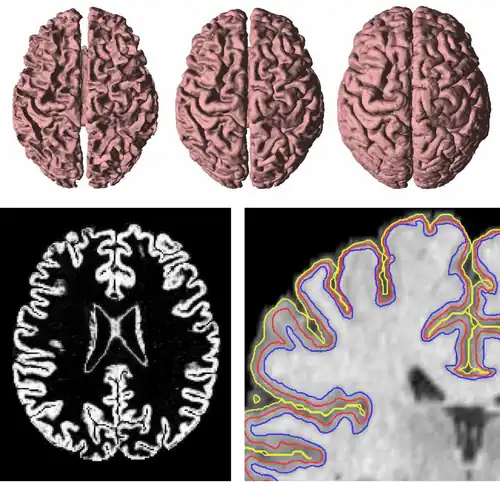

GVF has been used to find both inner, central, and central cortical surfaces in the analysis of brain images,[5] as shown in Figure 4. The process first finds the inner surface using a three-dimensional geometric deformable model with conventional forces. Then the central surface is found by exploiting the central tendency property of GVF. In particular, the cortical membership function of the human brain cortex, derived using a fuzzy classifier, is used to compute GVF as if itself were a thick edge map. The computed GVF vectors point towards the center of the cortex and can then be used as external forces to drive the inner surface to the central surface. Finally, another geometric deformable model with conventional forces is used to drive the central surface to a position on the outer surface of the cortex.